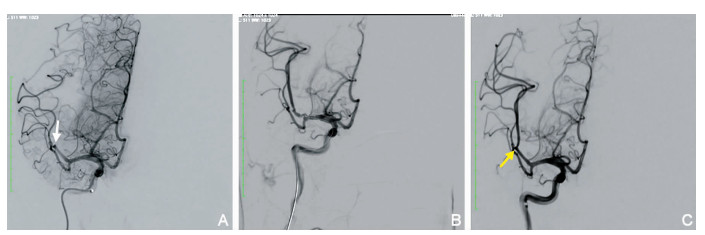

大脑中动脉M2段急性闭塞机械取栓疗效分析

朱余友, 王黎, 刘天龙, 张超, 宋建龙, 王朋, 孙文, 胡伟, 王国平

2021, 19(10): 1633-1636,1649. doi: 10.16766/j.cnki.issn.1674-4152.002129

摘要:

目的  探讨大脑中动脉M2段急性闭塞机械取栓治疗的疗效和安全性。  方法  回顾性收集2019年9月—2020年10月中国科学技术大学附属第一医院大脑中动脉M2段闭塞进行机械取栓的急性脑梗死患者20例。患者中男性8例,女性12例;年龄为32~84(62.5±14.4)岁;入院时美国国立卫生研究院卒中量表(NIHSS)评分(14±3)分;术前ASPECTS评分为8.0(7.0,9.0)分;病因分型采用TOAST分型,其中大动脉粥样硬化型2例,心源性栓塞10例,其他原因5例,不明原因3例;机械取栓前静脉溶栓6例,其中5例使用重组组织型纤溶酶原激活剂,1例使用尿激酶;优势M2患者14例;分析其手术方式、血管再通、颅内出血情况,并分析术后90 d预后。mTICI分级2b~3级为血管成功再通;mRS评分0~2分为临床预后良好。  结果  20例患者平均发病到股动脉穿刺时间为200~582 min,中位时间为370(277,483)min,发病到再通时间为(481.3±121.4)min;6例患者仅使用支架取栓,8例患者仅使用直接抽吸取栓,6例患者使用支架联合抽吸技术取栓,取栓次数为2(1,2)次;成功再通率为95.0%(19/20),4例患者发生颅内出血,其中2例为症状性颅内出血。90 d随访,20例患者中死亡1例,预后良好患者13例(65.0%)。单因素分析显示,联合静脉溶栓、不合并sICH与90 d良好预后相关。  结论  对大脑中动脉M2段闭塞急性缺血性卒中患者行机械取栓治疗具有安全性和有效性,联合静脉溶栓、不合并sICH与90 d良好预后相关。